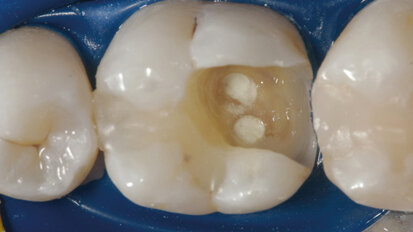

Hybridní terapie alignery